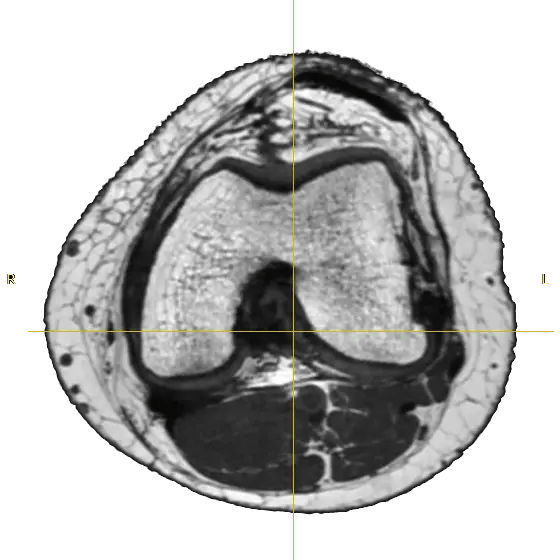

Using MRI scans of the human body and CAD, we design the orthotic shell around the soft tissues, using the movement patterns to fit the exoskeleton perfectly.

Although the regular orthoses are made by scanning the other shell of the knee, we decided to scan it inside also, to see the bone specificities and soft tissue parameters also.

take an MRI

slice up DICOM

voxel modell

segmented bone structure

make solid model

We used parametric modeling to build a surfacee model to the bones. Steb by step process below.